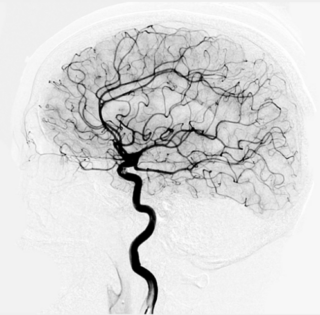

Endovascular embolization is a minimally invasive treatment for vascular malformations including AVMs and AVFs. It is not a treatment for cavernous malformations or DVAs. Endovascular embolization is typically performed under general anesthesia under the direction of specially trained Neuro-anesthesiologists. A small plastic tube called a catheter is placed into a blood vessel, usually in the groin, and then is guided by using X-rays into the brain and ultimately inside the vascular malformation. Special glue or other materials are then injected into the vascular malformation to reduce or eliminate blood flow to the vascular malformation. Endovascular embolization cures many vascular malformations, while in others the treatment is used to make surgery or radiosurgery safer and more effective.